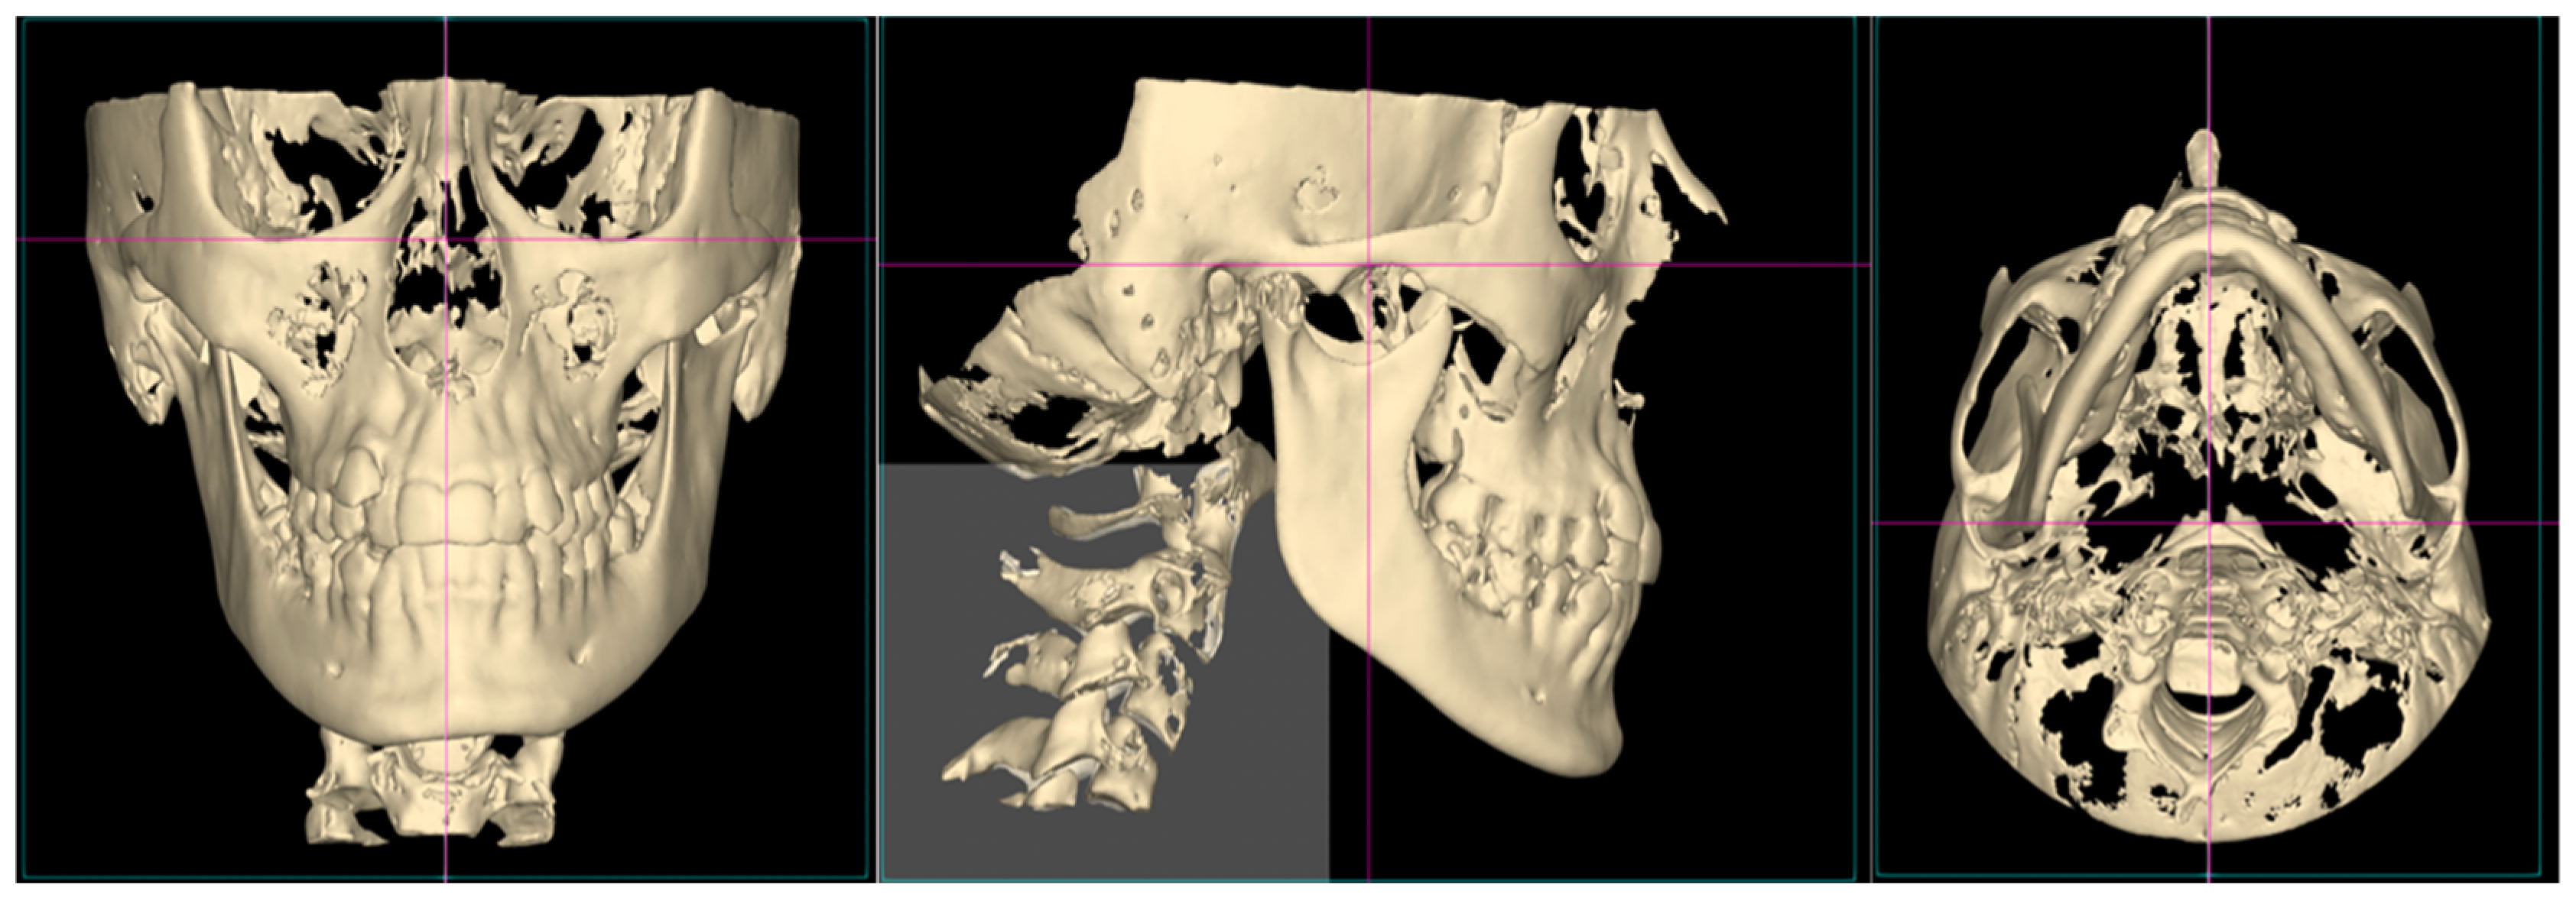

2.1. Airway Volume Calculation

2.2. Condyle Volume Calculation